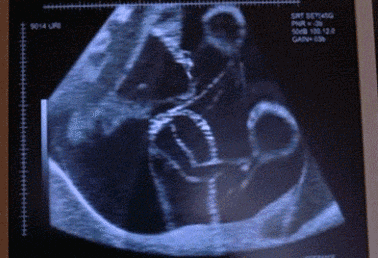

昨天,王力宏发微博晒出刚生产完的老婆李靓蕾,和二胎女儿的新生照,一家人好温馨。曝光20明星大尺度床戏 真实堪比不雅视频图

今天一早,“古装男神”乔振宇又传来喜讯,老婆王倩一生下女儿,老乔一子一女好福气!